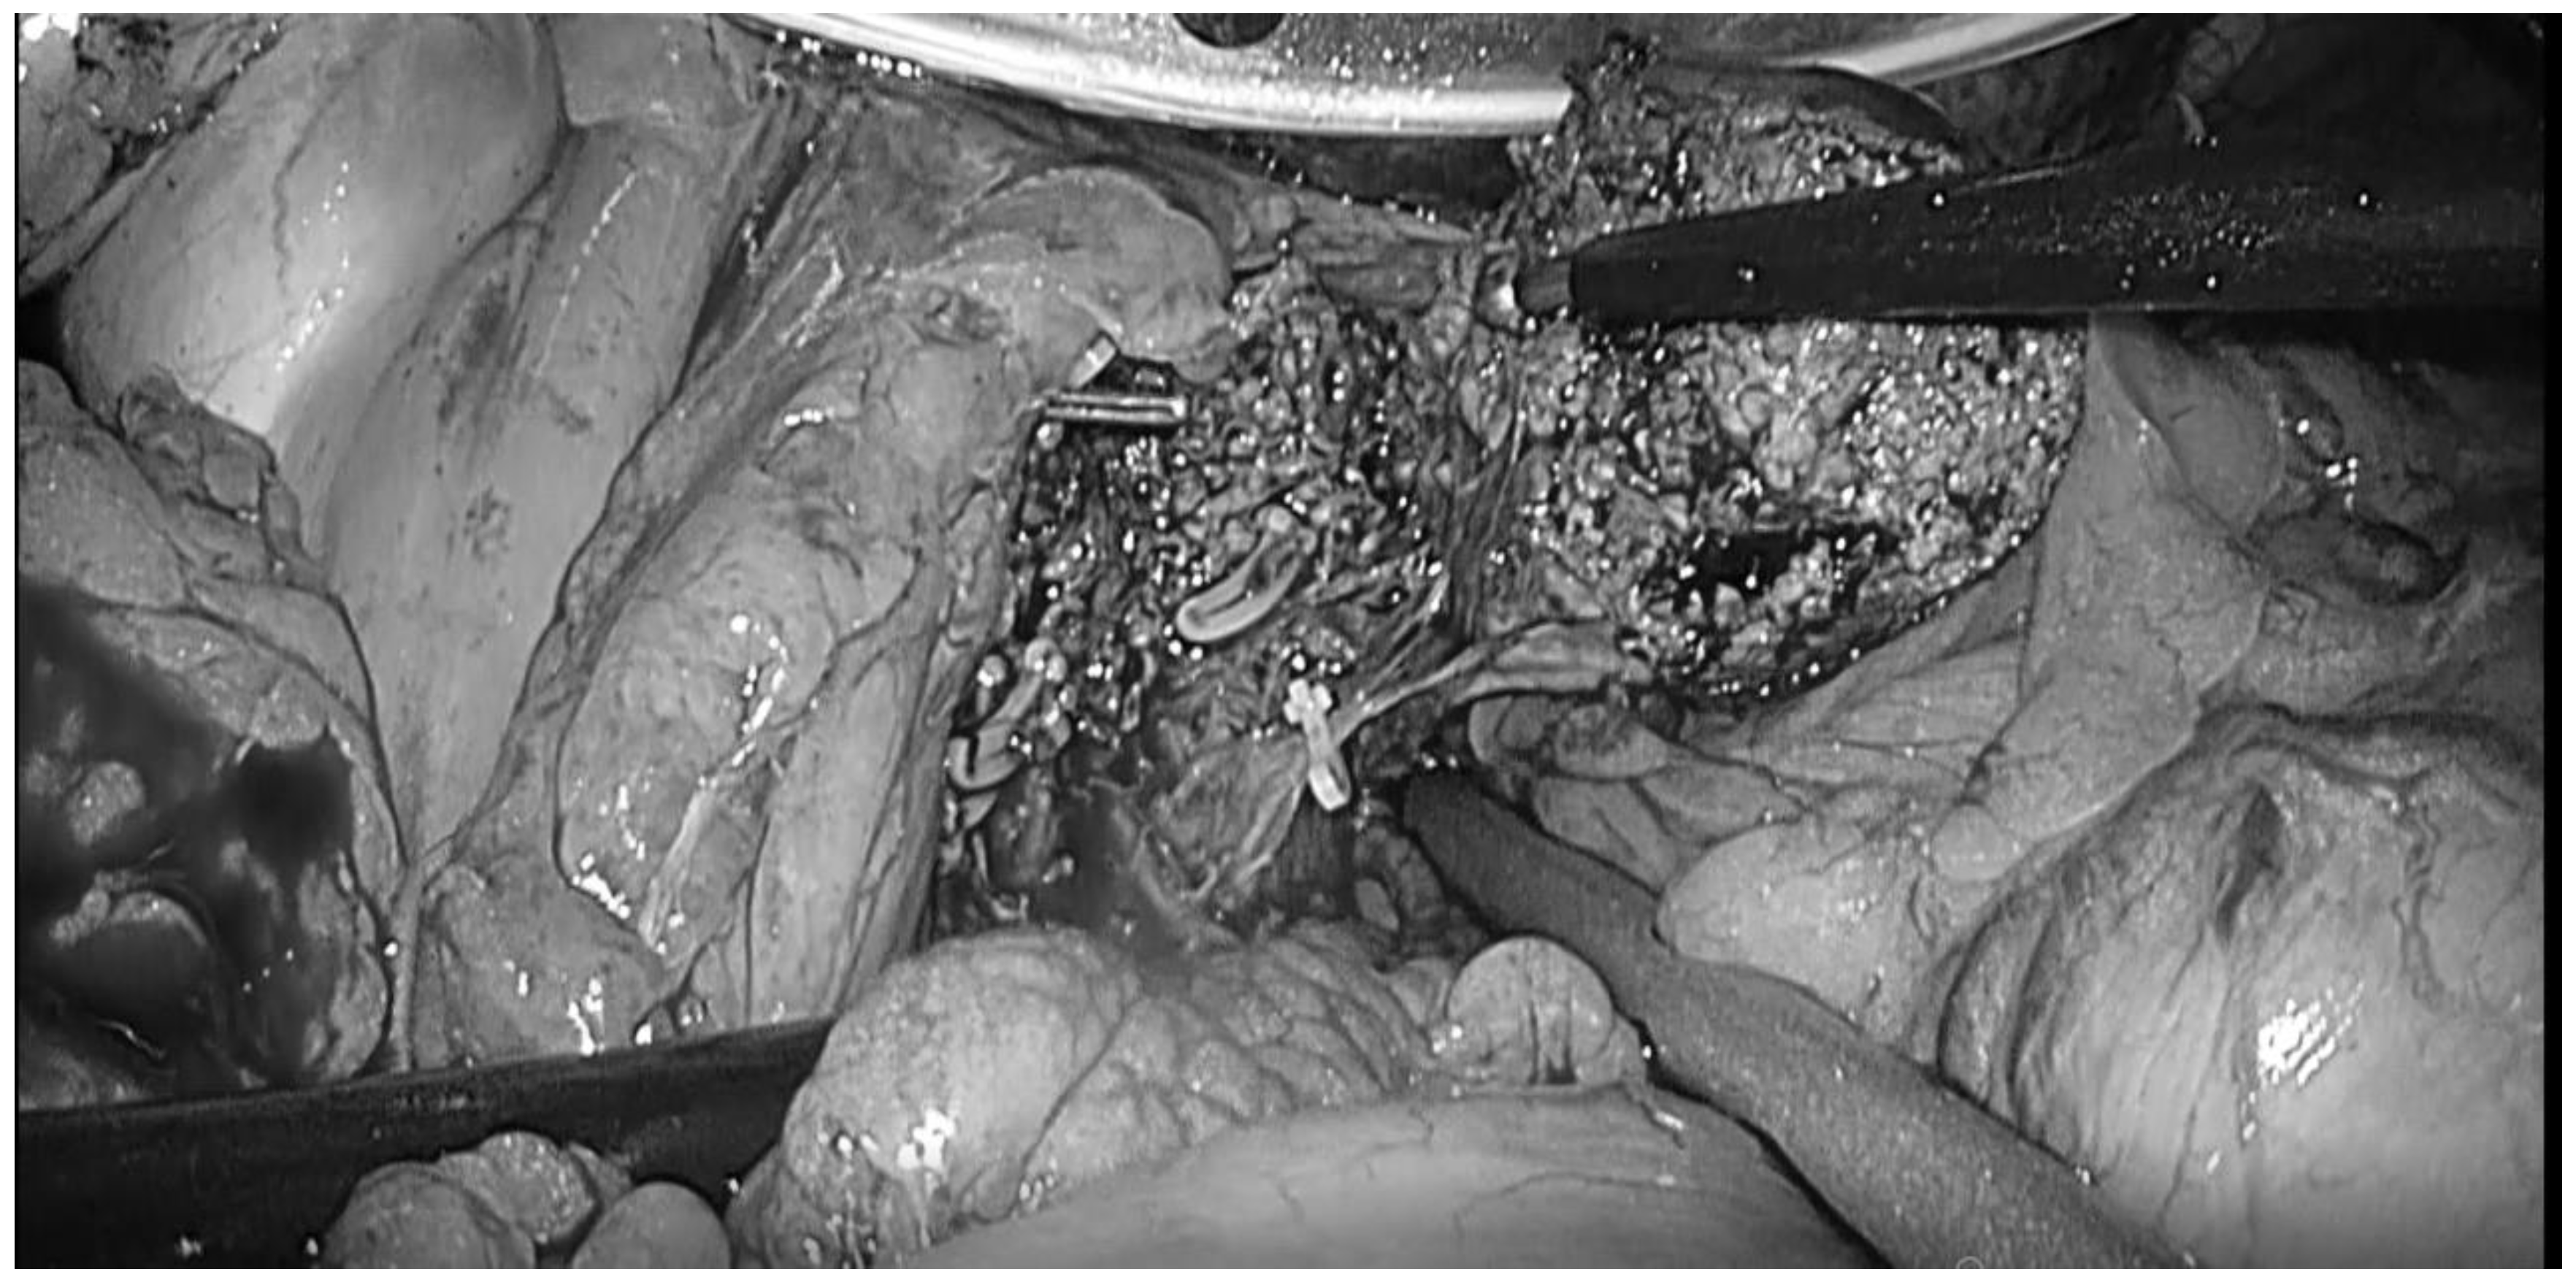

- Kinoshita, M.; Tanaka, S.; Kodai, S.; Takemura, S.; Shinkawa, H.; Ohira, G.; Nishio, K.; Tauchi, J.; Kanazawa, A.; Kubo, S. Increasing incidence and severity of post-hepatectomy adhesion around the liver may be influenced by the hepatectomy-related operative procedures. Asian J. Surg. 2023, 46, 228–235. [Google Scholar] [CrossRef]

- Kinoshita, M.; Kanazawa, A.; Kodai, S.; Shimizu, S.; Murata, A.; Nishio, K.; Hamano, G.; Shinkawa, H.; Tanaka, S.; Takemura, S.; et al. Difficulty classifications of laparoscopic repeated liver resection in patients with recurrent hepatocellular carcinoma. Asian J. Endosc. Surg. 2019, 13, 366–374. [Google Scholar] [CrossRef]

- Kinoshita, M.; Kanazawa, A.; Tanaka, S.; Takemura, S.; Amano, R.; Kimura, K.; Shinkawa, H.; Ohira, G.; Nishio, K.; Kubo, S. Indications of Laparoscopic Repeat Liver Resection for Recurrent Hepatocellular Carcinoma. Ann. Gastroenterol. Surg. 2021, 6, 119–126. [Google Scholar] [CrossRef]